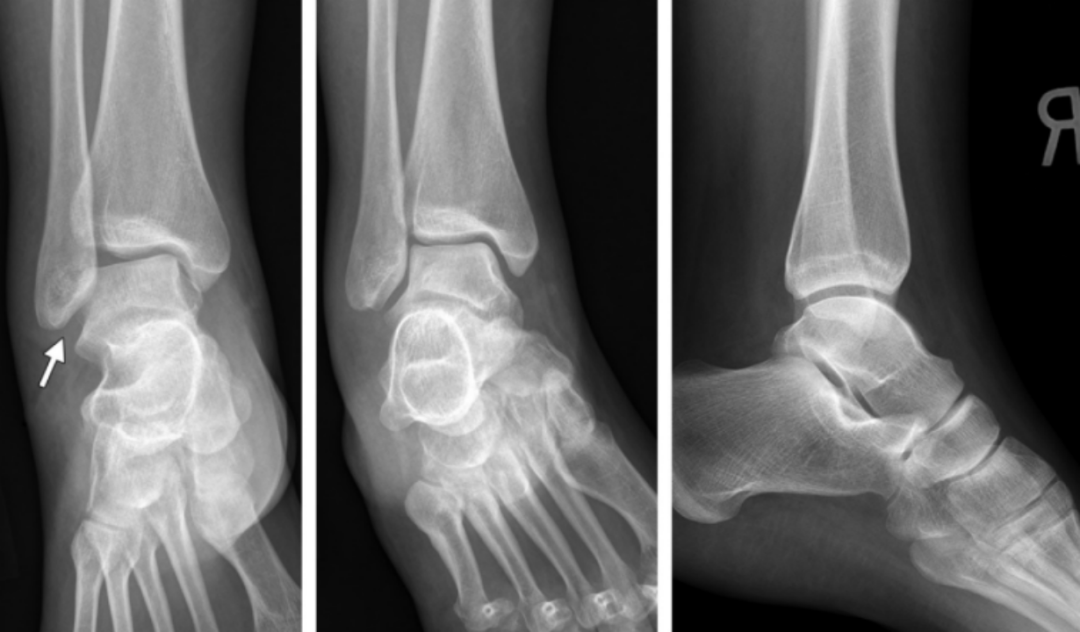

1、旋后(内翻)内收损伤(简称 SA)

损伤时,足呈旋后位,距骨内收,使踝关节外侧韧带紧张。

旋后内收损伤

Ⅰ度:首先发生的是外侧副韧带撕裂或者外踝的撕脱骨折,由于损伤发生于下胫腓联合远端,该韧带多保持完整。

I 度损伤 X 线显示:外踝间隙增宽,提示外侧副韧带撕裂,未见胫腓骨骨折,此型在 X 线上是隐匿的。

Ⅱ 度:内收的外力继续作用,内踝受内翻的距骨挤压作用,可造成内踝的垂直骨折,及胫骨远端关节面的内侧部分压缩骨折,如果合并其他方向的外力,有可能造成内踝的斜行骨折。

II 度损伤 X 线片显示:腓骨骨折在下胫腓联合水平以下,内踝垂直骨折;侧位 x 线片显示后踝无骨折。